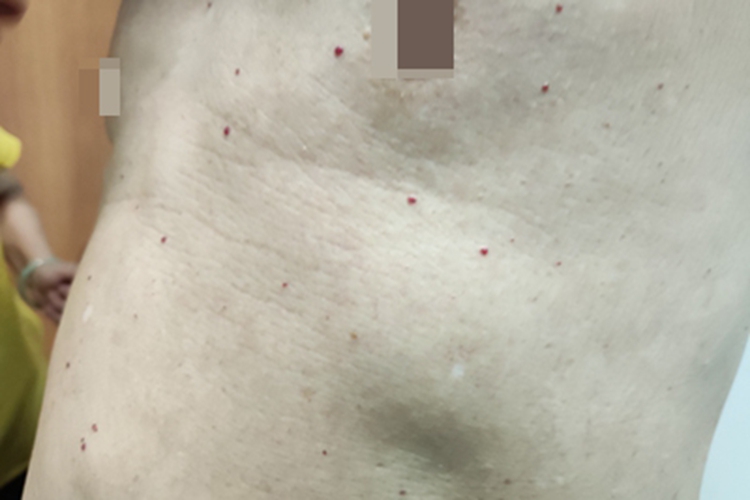

毛细血管瘤患者常见表现为红点,可发生于身体各部位,通常鲜红色,可相互融合形成片状,与原有血管扩张有关,多数不必治疗。

毛细血管瘤症状多见于婴儿或幼儿,通常发于头面部,也可发于其他部位。于出生后3-18个月开始发病,表现为鲜红的红点,表面光滑,隆起于皮肤,通常为单发,也可相互融合形成片状。表面比较薄,如用力擦洗可能被碰破出血,但很快结痂、止血。经过1-4年血管瘤可见消退,4岁后可望完全吸收消退,不残留痕迹。